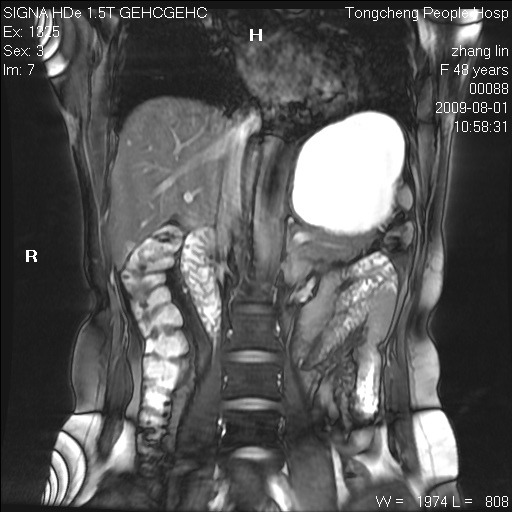

女,48岁。健康体检,彩超发现右肾占位性病变。平素健康。

临床诊断:右肾占位性病变,性质待定(囊肿?肿瘤?)。

上中腹部mr平扫+增强扫描,图像如下:

右肾上极见一类圆形病灶,t1wi呈等信号t2wi呈等高混杂信号,三期增强无强化,边界清---考虑囊肿出血。